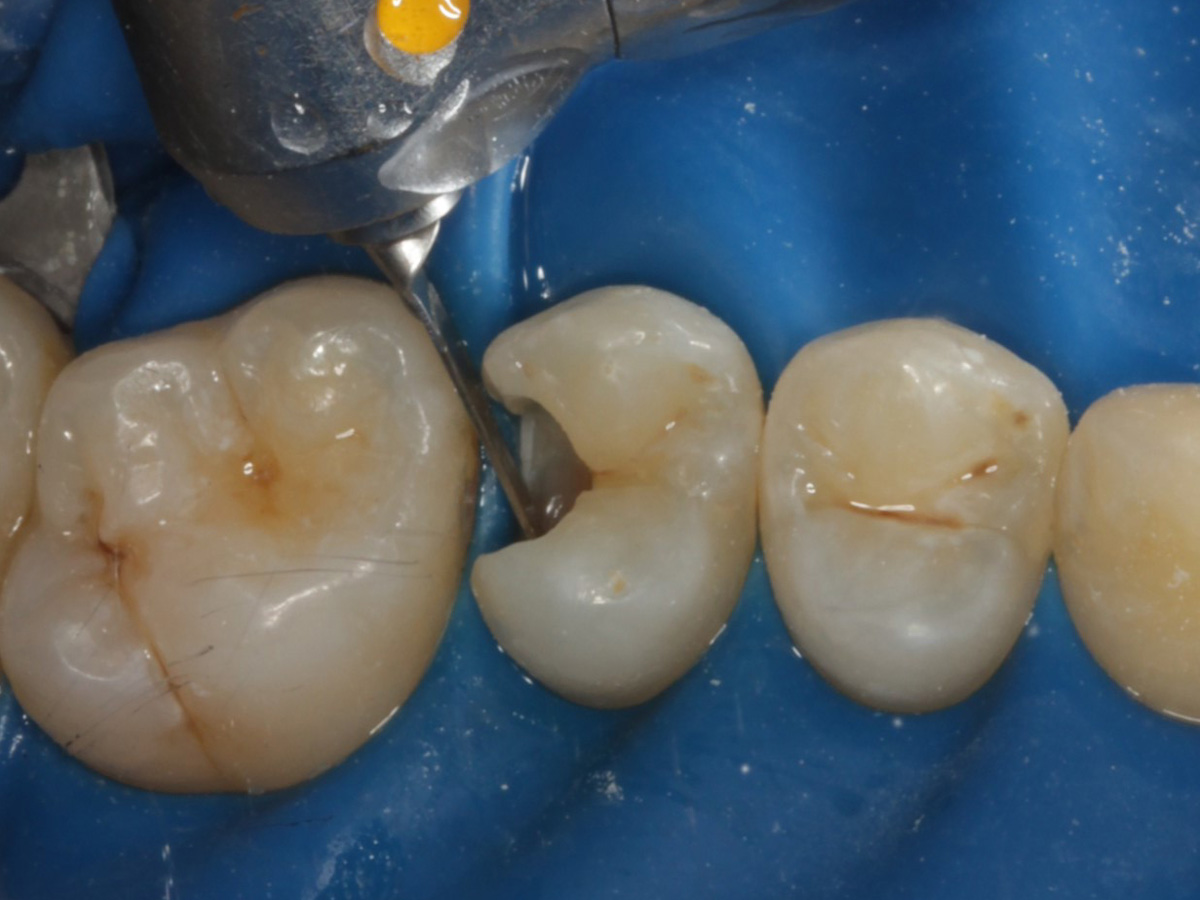

Abbildung 6

Kariesexcavation pulpennah mit Kunststoffrosenbohrer